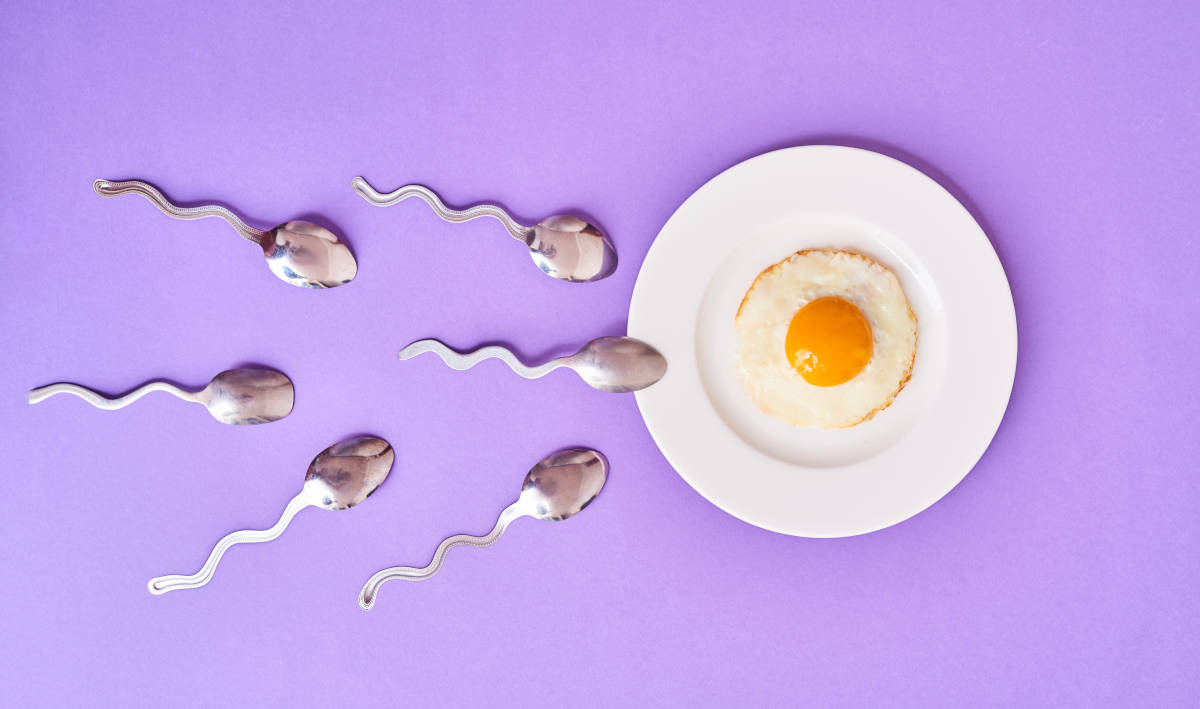

Perkembangan janin merupakan proses yang rumit dan istimewa. Proses ini dimulai bahkan sebelum seorang wanita tahu bahwa dirinya hamil hingga melahirkan. Di antara pembuahan dan kelahiran ada berbagai proses yang rinci, detail, dan sistematis.

Mengetahui perkembangan janin dari minggu ke minggu penting dilakukan agar Mums maupun calon ibu bisa memahami sebuah proses panjang yang rumit dan sistematis terbentuknya manusia. Tentu saja agar bisa menjaga kehamilan dengan pola hidup sehat. Sehingga ibu dan bayi selamat hingga saatnya dilahirkan.

Berikut ini perkembangan janin dari minggu ke minggu yang Mums harus tahu :